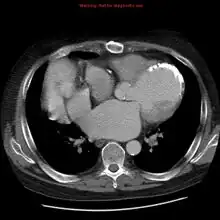

CT chest: demonstrates the left anatomic connections in a heterotopic transplant